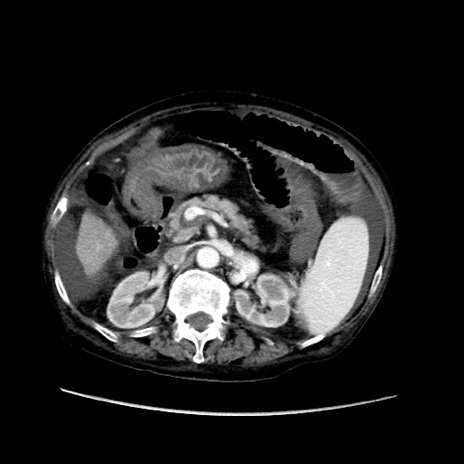

症例31(横断像)

【症例】80歳代 女性

【主訴】腹部膨満感

【現病歴】他院にて肝硬変にてフォロー中。1週間前から便秘、腹部膨満感、臍部腫瘤あり受診となる。

【既往歴】肝硬変

【身体所見】腹部膨隆あり、皮膚変化なし、疼痛なし。

【データ】WBC 4600、CRP 0.25